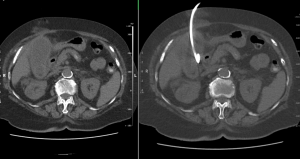

Chemická lumbální sympatektomie pod CT (CHLSE)

Co je chemická lumbální sympatektomie pod CT kontrolou?

Co se vlastně při CHLSE odehrává?

Při výkonu budete ležet na břiše, a nebudete se hýbat, celý výkon trvá většinou 15 – 20 minut, výjimečně déle. Zezadu lékař zavede tenkou jehlu (tenčí než na odběr krve) do místa, kde probíhají kmeny sympatického nervstva (vedle páteře) a injektuje léčebnou směs sestávající z alkoholu, anestetika a malého množství kontrastní látky, celkové množství směsi je okolo 13 ml. Aplikace směsi může být spojena s nepříjemnými zážitky – většinou bolestmi do břicha či do zad, též se můžete celkově potit. Poté, co je směs umístěna, lékař vytáhne jehlu a místo přelepí.